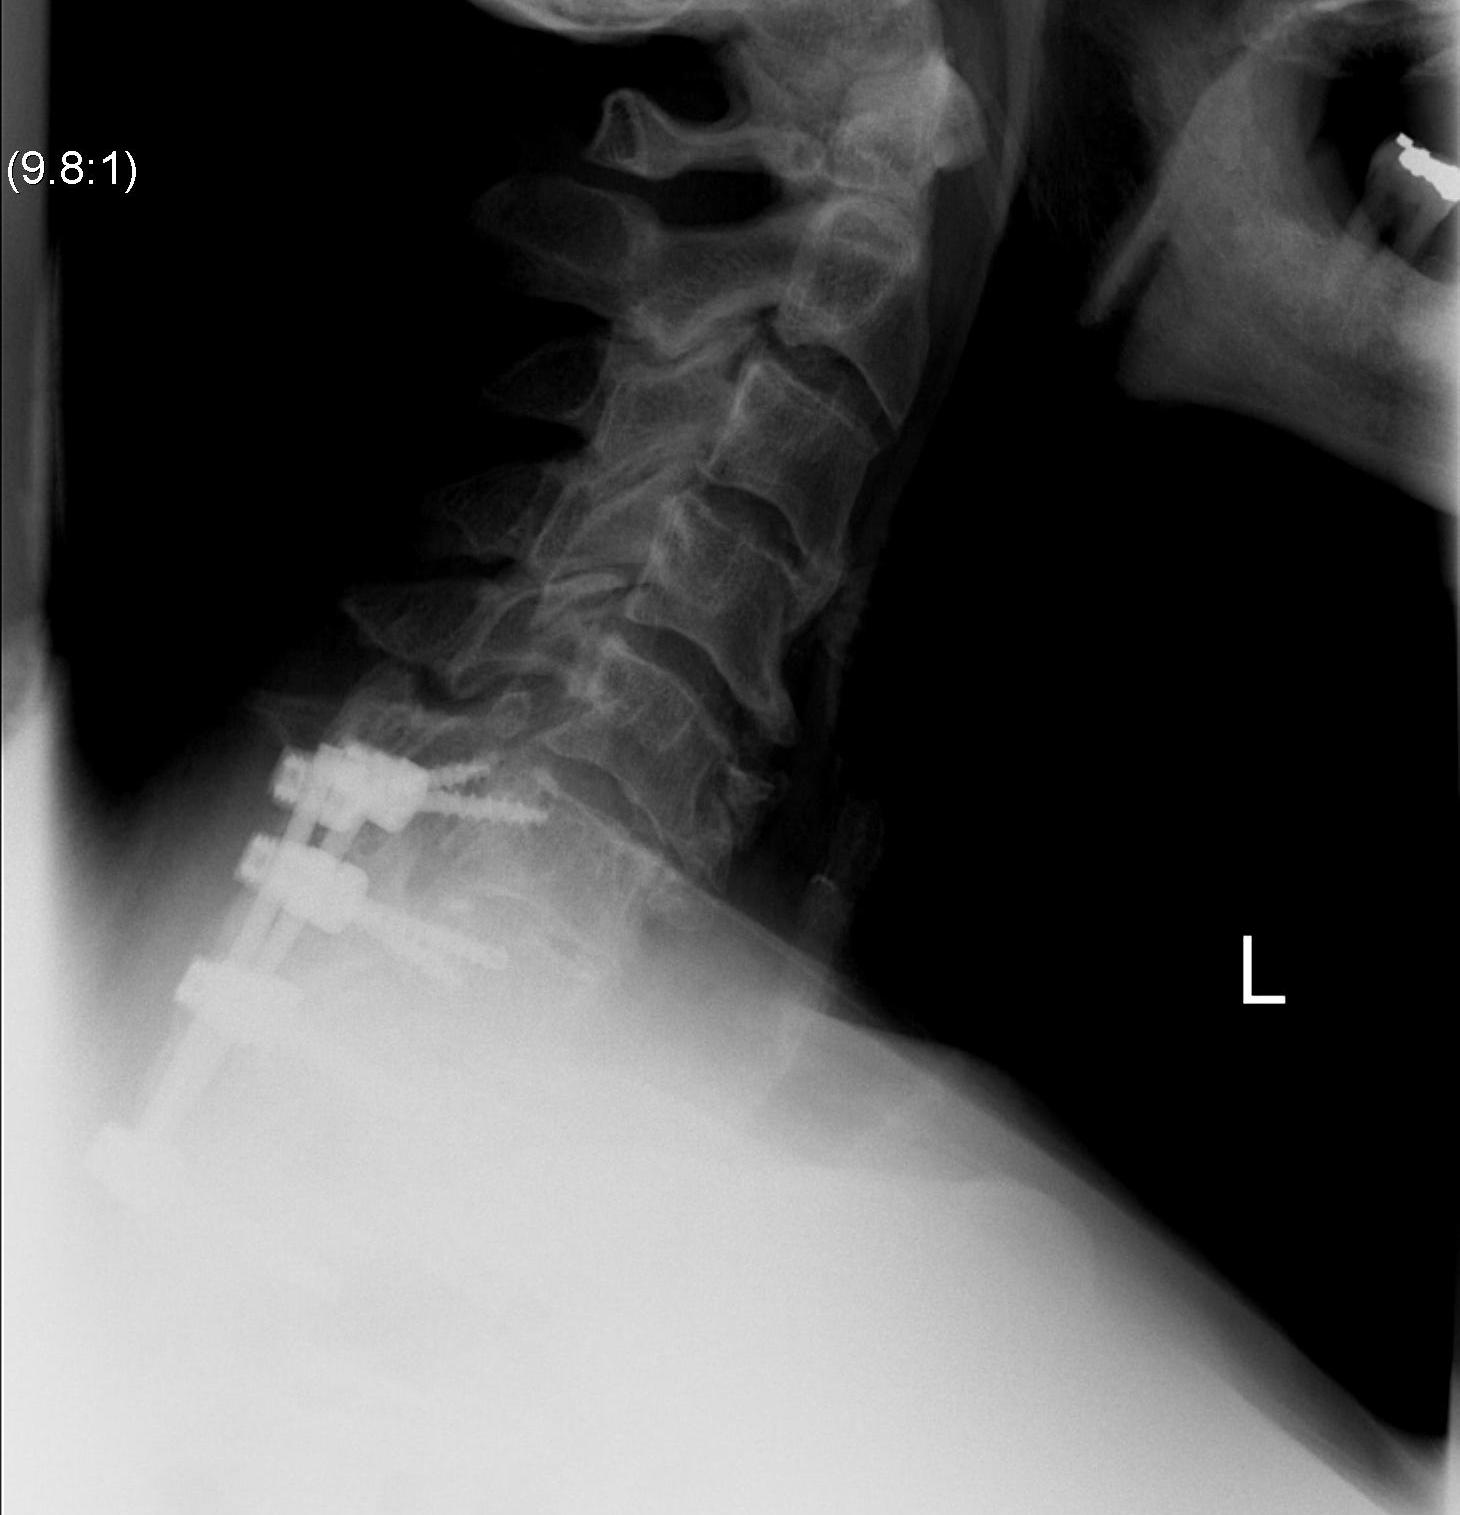

Options

ACDF

Posterior laminectomy and fusion

Anterior decompression and fusion

May need long fusion to prevent SAS above and below